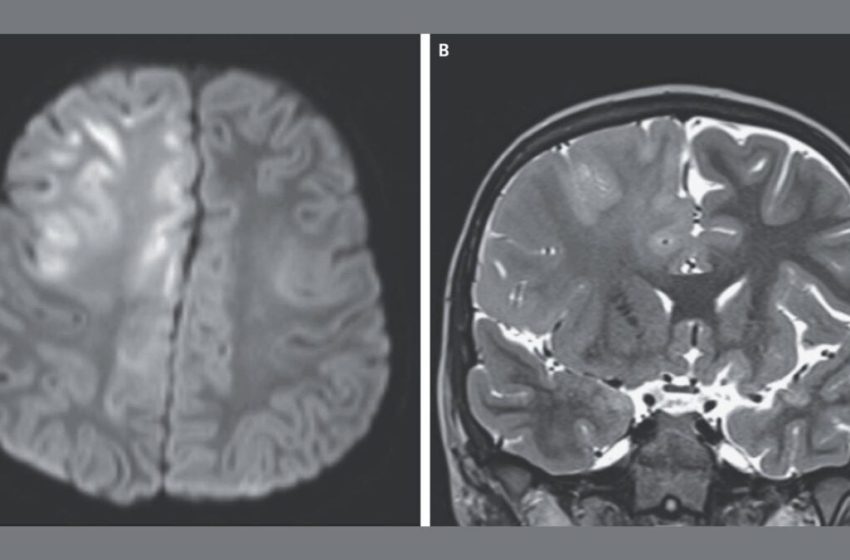

In this case, the 7-year-old boy visited the doctors three months into having seizures and cognitive decline. He was no longer able to speak, and an MRI scan (seen in the top image) revealed extensive damage to the brain. The boy had contracted measles at 7 months of age while living in Afghanistan, a country where the virus is endemic. Tests of his spinal fluid revealed high levels of antibodies to the measles virus. That, coupled with his infection history and EEG results, led doctors to diagnose him with SSPE.